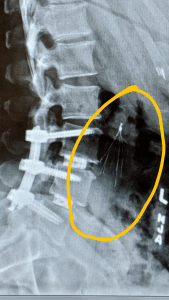

I was freaked out big time about the clots. After all, everyone knows the damage blood clots can do. Plus, I was terrified of being on bed rest — how much progress would I lose by missing physical therapy? I cried — tears of fear and tears of frustration. My surgeon and now my hematologist decided I needed an inferior vena cava (IVC) filter placed to catch the DVT should they decide to move. That was placed while under twilight anesthesia (I remember none of the procedure). A small incision was placed in a vein on my right collarbone and the filter threaded through there until it was placed properly. Once it was placed, my bed rest restrictions were lifted. I was also switched to a different blood thinner. I started getting Lovenox injections. Those were worse that the heparin shots, let me tell you! Both blood thinner injections are given normally in the belly, and they can leave significant bruising. The Lovenox injections also had the added “fun” of burning like hell upon injection. I started having to have an ice pack on my belly 15 minutes before an injection to help minimize the burning. Luckily, once I was discharged home, I was switched to an oral blood thinner (Eliquis).